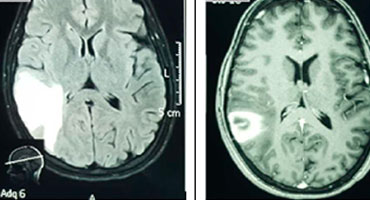

Trombosis de senos venosos durales: análisis clínico y neuroradiológico de 10 casos consecutivos en el Hospital México entre enero y diciembre del 2013.

La trombosis de senos venosos durales (TSVD) es una emergencia neurológica poco común y potencialmente mortal. Su incidencia anual se estima...